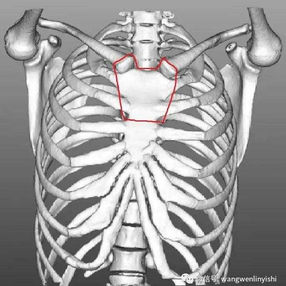

The patient’s thoracic spine is unnaturally flat with a slight forward curvature at the upper thoracic vertebrae, reducing the distance between it and the anterior chest wall. Additionally, the ascending aorta is dilated, and the trachea is noticeably compressed, particularly severely at the start of the aortic arch. The patient was ultimately diagnosed with flatback syndrome combined with severe tracheal stenosis.

Flatback syndrome is an extremely rare spinal deformity characterized by a flattened thoracic spine and a loss of natural spinal curvature. This significantly narrows the space between the thoracic spine and the anterior chest wall, leading to a reduced volume of the chest cavity and compression of the mediastinum. Consequently, complications such as the displacement and compression of the heart, major blood vessels, and trachea may arise. Typically, while symptoms can be managed with conservative treatments, surgical intervention is required when these methods are proven to be ineffective.